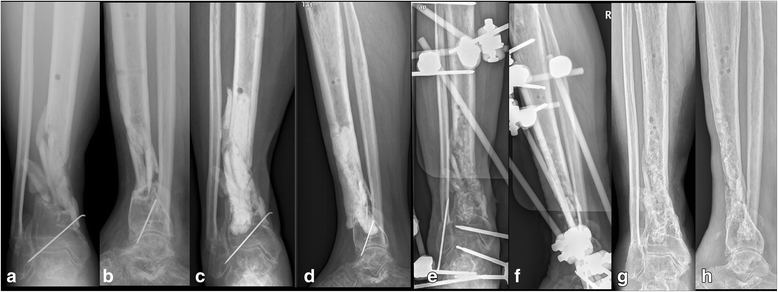

Methods: We retrospectively analysed 40 patients with post-traumatic osteomyelitis of the tibia who underwent treatment, which was performed in two stages. In the first stage, thorough debridement was performed, and bone defects were filled with either antibiotic-impregnated cement beads (bead group, 18 patients) or spacers (spacer group, 22 patients). In the second stage, the cement beads or spacers were removed (for the spacer group, the induced membrane formed by the spacer was preserved) and the bone defects were filled with cancellous autografts.

Results: All patients in the bead group had small/partial segmental bone defects after debridement, while 3 patients in the spacer group had large/segmental bone defects. The mean volume of bone defects of the spacer group (40.4 cm3) was significantly larger than that of the bead group (32.4 cm3). The infection control rate (88.9%,16/18 vs 90.9%, 20/22), bone healing time (8.5 months vs 7.5 months) and complication rates (22.2%, 4/18 vs 27.2%, 6/22) were comparable between bead group and spacer group.

Conclusion: The results of this study suggest that cement spacers may have an infection control rate comparable to cement beads in the treatment of bone defects associated with post-traumatic osteomyelitis. Furthermore, cement spacers could be used for the reconstruction of small/partial segmental bone defects as well as for large/segmental bone defects, whereas cement beads were not suitable for the reconstruction of large/segmental bone defects.